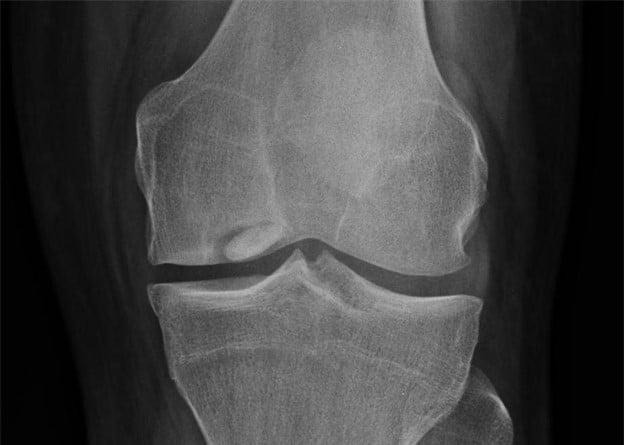

Juvenile Osteochondritis Dessicans

Despite the nomenclature, the disease process is related to bone delamination and necrosis rather than cartilaginous injury or disease. Lateral aspect of the medial condyle of the femur is the most common site. This condition is not unique to athletes. Plain radiographs are indicated if the condition is suspected, as the lesion will be demonstrated as an area of lucency on x-ray. MRI may be obtained to assess for additional injury, as well as more detailed evaluation of the chondral lesion. However, this may be more useful in adults as compared to children and adolescents.9 The criteria for use in children have not yet been well defined, and adult criteria may not be applicable.10 Patients often present with anterior or medial knee pain. There may be small effusion on exam and often, but not always, tenderness to palpation of the femoral condyle. If a lesion is visualized, rest and activity restriction is the approach of choice and typically leads to spontaneous resolution in 8-12 weeks in children. The patient should be pain free, and x-ray should demonstrate healing. Spontaneous resolution is more common in children and adolescents than in adults. Knee immobilization can be indicated in severe cases as can surgical intervention for unstable versions.9 Stable lesions without adequate healing in 3-6 months warrant evaluation by an orthopedic surgeon for possible operative intervention.11

Case courtesy of Dr. Maulik S. Patel, Radiopaedia.org. From the case rID: 10668